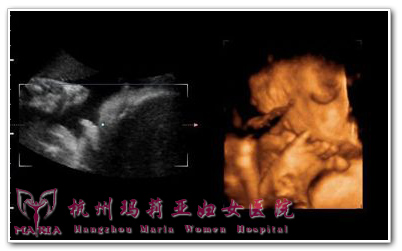

玛莉亚超声科钱主任说,做四维彩超也是有较好时间的,一般来说,单胎四维彩超的较好时间是23—27周,双胎的较好时间是22-23周。同时,四维彩超的效果清不清楚,和肚子里宝宝是不是“配合”很有关系。如果宝宝的脸部有遮挡物,那就很难看见面部表情。宝宝自己的手脚,或者是胎盘、脐带、子宫壁等,都是遮挡物。如果宝宝的脸部前面没有适量的羊水,四维彩超的效果也不会很好。因为羊水是很好的透声窗,四维彩超是要通过透声窗来看宝宝的,所以如果妈妈的羊水少,四维彩超出来的效果也会相对差一点。

玛莉亚专家介绍,四维彩超主要是确定胎儿是否存活、胎儿数目、胎位和胎动情况,羊水量的测定,观察颅脑、四腔心、脊柱、胃、双肾、膀胱等结构是否存在;估计胎儿超声孕龄,能对胎儿畸形做粗略的筛查。另外,四维彩超不仅能够多方位、多角度地观察宫内胎儿的生长发育情况,还能为早期诊断胎儿先天性体表畸形和先天性心脏疾病提供准确的科学依据。

排畸功能的医学筛查功能:四维彩超能够对胎儿进行超声检查能立体显示胎儿的颜色、面、各器官的发育情况,甚至胎儿在母体里的状态也可以观察到;对胎儿畸形,如唇裂、腭裂、骨骼发育异常、心血管畸形等能早期诊断。